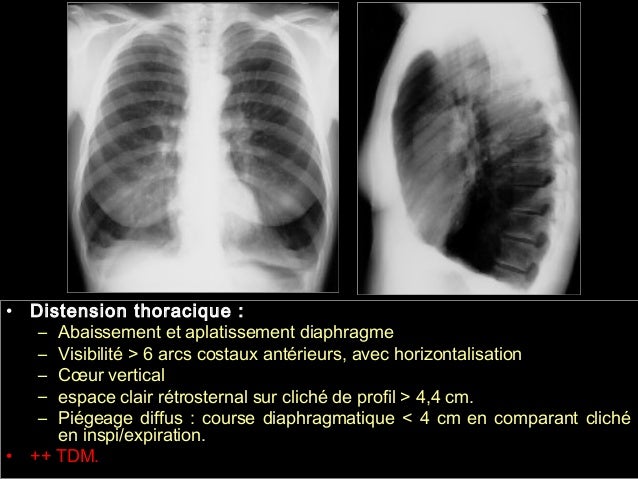

Résec bulle emphysème réduc vol pulm thortomie;. Bulle d’emphysème RP bulle d’emphysème L’emphysème diffus donne assez souvent après un certain temps d’évolution, une destruction des structures entre les alvéoles qui aboutissent à des communications entre alvéoles et bronchioles pour former ce qu’on appelle des bulles. La chirurgie (ablation chirurgicale) des régions emphysémateuses non fonctionnelles ou des bulles d’emphysème qui peuvent comprimer le poumon, dans quelques cas précis.

Dans le cadre d'un emphysème pulmonaire, les alvéoles voient leur élasticité se modifier jusqu'à parvenir à ce que l'on nomme une distension pulmonaire, entraînant alors une diminution de l. Bonjour, J'ai 30 ans fumeur depuis 15 ans (tabaccannabis) et on vient de me diagnostiquer un emphysème bulleux (plein de petits à gauche et une bulle de 9cmx4 Maladies Respiratoires Bpco Emphysème Maladies Respiratoires Bpco Emphysème Vous souhaitez réagir à ce message ?. Définitions de bulle d'emphysème pulmonaire, synonymes, antonymes, dérivés de bulle d'emphysème pulmonaire, dictionnaire analogique de bulle d'emphysème pulmonaire (français).